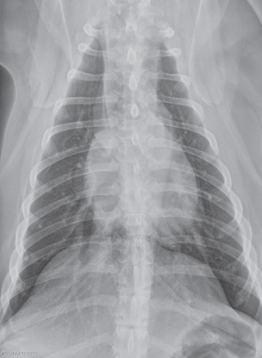

VD

DV

Expiration

inspiration